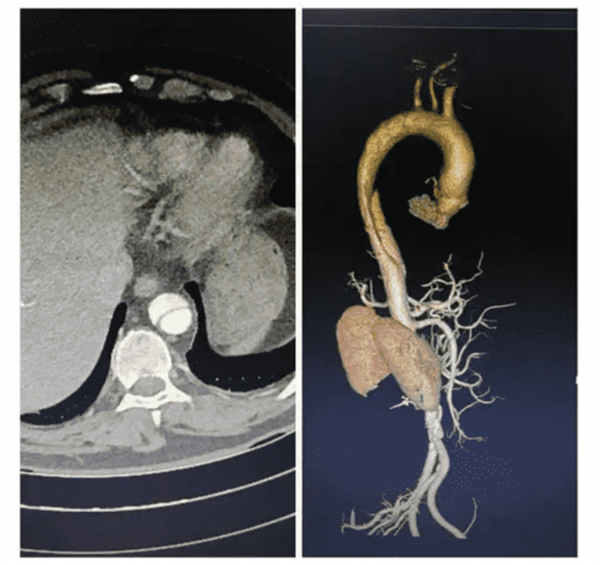

• 全球首款!浙大一院、阿里发布主动脉急诊AI模型:准确率高达99.4%

电脑知识网8月27日消息,浙江大学医学院附属第一医院、阿里巴巴达摩院发布了全球首款用于胸痛急诊场景的AI模型“iAorta”,可用常规平扫CT在几秒内识别急性主动脉综合征,将确诊时间缩短至2小时内。 实际应用中,iAorta从1万多名胸痛患者中精准发现了21例,并及时救治。 主动脉是人体最重要的血管,其夹层、壁间血肿、穿透性溃疡等结构…